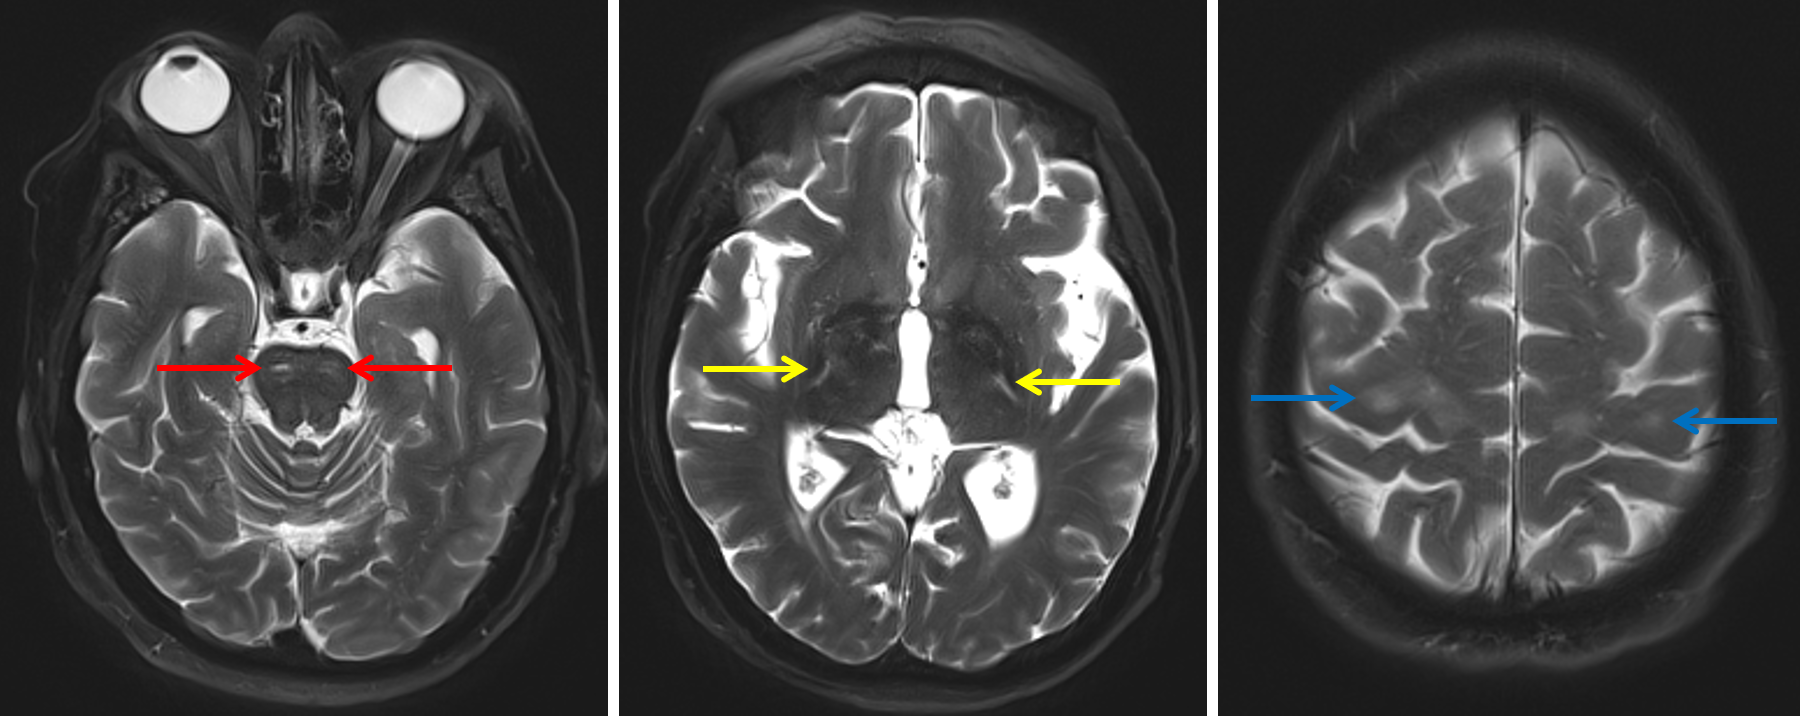

Age: 54

Sex: Female

Indication: Concern for upper motor neuron disease

Amyotrophic lateral sclerosis (ALS)

Sample ReportAbnormal T2/FLAIR signal hyperintensity along the bilateral corticospinal tracts extending from the precentral gyri through the internal capsules and into the brainstem, which raises concern for an upper motor neuron degenerative disease like amyotrophic lateral sclerosis (ALS).